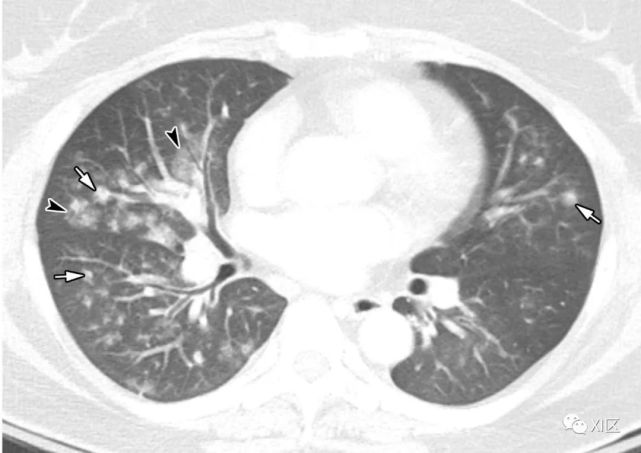

HPIV肺炎CT表现为多灶性斑片实变影伴GGO,使区分病毒与细菌性肺炎更加困难,约四分之一的患者表现为中央小叶结节伴支气管壁增厚。

图14 一位22岁女性感染前1个月因急性淋巴细胞白血病接受单倍体相合骨髓移植治疗,有发热,诊断为 HPIV病毒性肺炎。

在主支气管水平(上)和叶间区水平(中上)的初始轴位胸部CT图像显示沿支气管血管束和轻度支气管壁增厚(箭头)的多灶性不明确结节性GGO病变(箭)。中性粒细胞减少持续存在。(中下,下)随访10天后获得的轴位胸部CT图像显示病变的范围和强度增加,并沿支气管血管束增加不规则的实变结节(箭)。尽管进行了重症监护,该患者仍然死亡。